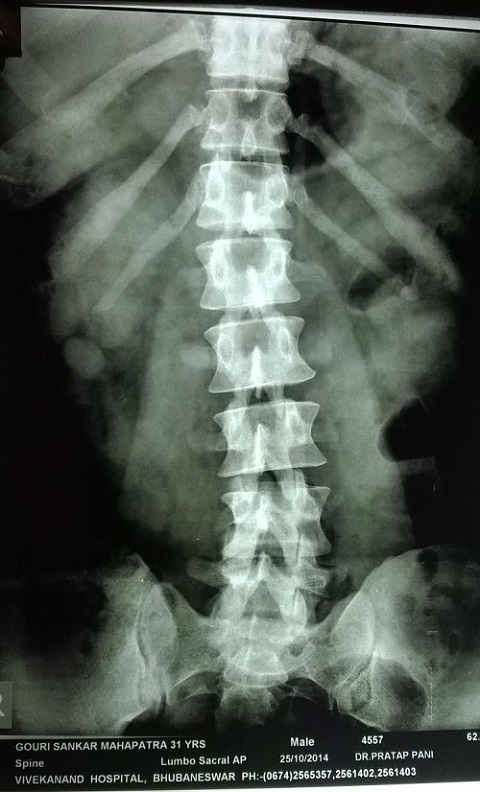

X-Ray of Gouri Shankar Mohapatra